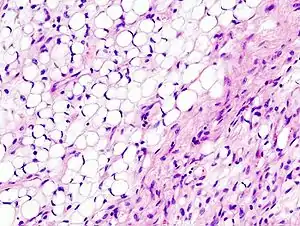

Histopathologic image of myxoid liposarcoma arising in the deep soft tissue of the thigh. H & E stain.

A myxoid liposarcoma is a cancerous soft tissue tumor that typically presents as a large, painless lump.[1]

Myxoid liposarcomas are the second-most common type of liposarcoma, representing 30–40% of all liposarcomas in the limbs, occurring most commonly in the legs, particularly the thigh, followed by the buttocks, retroperitoneum, trunk, ankle, proximal limb girdle, head and neck, and wrist. They occur in the intermuscular fascial planes or deep-seated areas. They present as a large, slow-growing, painless mass.[2]